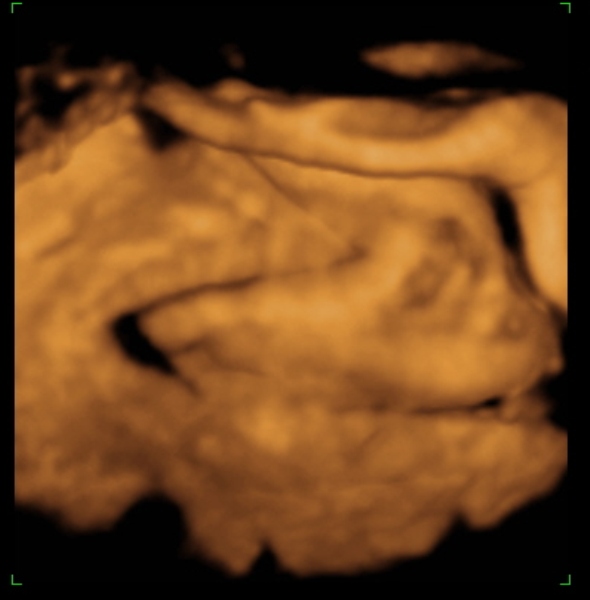

Tegnap megjártuk a 4D-t, nagyon szép husis a kisasszony :lol: persze aludt, nem kommunikált velünk, akármit ettem, ittam, csináltam. :lol: De azért féloldalasan aludt, úgyhogy csak láthattuk, volt mosoly, ásítás, fintor :lol: :lol:

Ja, és itt is megállapították, hogy nagy a talpa :lol: :lol: :lol: És a fejecskéje is, úgyhogy azt mondták majd megdolgoztat szülésnél, gondoltam "tök jó" :lol: :roll:

Tappancs - 7,1 cm :lol: :lol: (s azt mondta a nő, hogy a talp általában ugyan akkora, mint az FL, tehát Dorkáé, nagy pacsker :lol: )

Ja, és a képek lemaradtak :D

Kép nagy tapppppancsom:)

Persze a kis keze mindenhol ott van :lol: Bocsi, ha picit sok voltam :oops: 8)